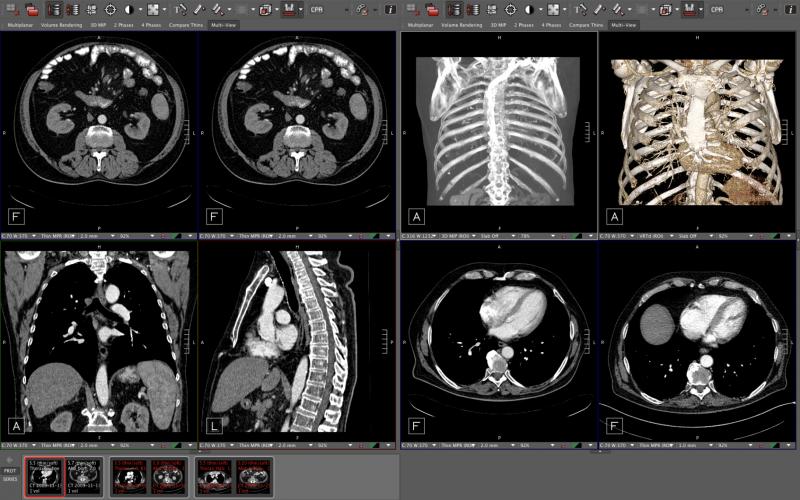

Philips integrated the IntelliSpace Portal advanced applications with the Philips diagnostic viewer (from Carestream) creating a combined radiology diagnostic workspace.

The Philips diagnostic workspace anticipates the radiologist’s next move to speed workflow. In the case of serial computed tomography (CT) scans of cancer patients to track tumor size during treatments, the system can automatically call up prior exams for comparisons. It also automates finding the exact same view the radiologist has chosen, and standardizes and automates the tumor quantification processes to show if the tumor is shrinking or getting larger.